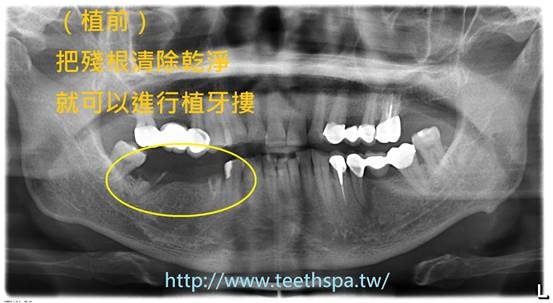

別讓殘根壞了你的人生 新禾牙醫診所 植牙 專業植牙 人工植牙 微創植牙 無痛植牙 全口植牙